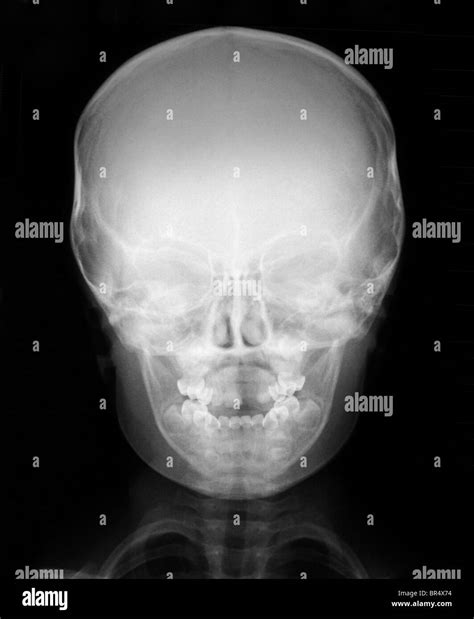

Infant X-ray imaging involves the use of low-dose radiation to produce images of the internal body structures. This technique is particularly useful for diagnosing conditions such as fractures, pneumonia, and congenital anomalies. The process is quick and relatively painless, making it suitable for infants who may be too young to cooperate with more complex diagnostic procedures.

Interpreting infant X-ray results requires expertise and experience. Radiologists are trained to identify abnormalities and provide accurate diagnoses. Here are some key points to consider:

• Radiologist Review: The X-ray images are reviewed by a radiologist, who will look for any signs of fractures, infections, or other abnormalities.

• Report Generation: A detailed report is generated, outlining the findings and recommendations for further action.